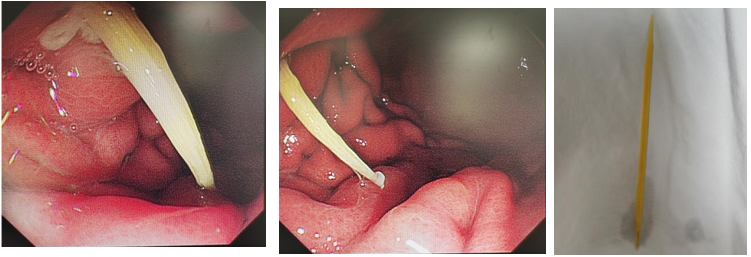

高某某,入院前2天饮酒后出现上腹部疼痛不适,伴腹胀、恶心,无呕吐,无腹泻,无明显放射痛,进食和休息后稍缓解,需进一步行胃镜检查明确。5月20日患者行胃镜检查发现“胃体前壁可见一条状异物刺入胃壁,局部粘膜肿胀明显,可见脓液覆着”,考虑到针刺样异物,刺入胃壁较深,随时有穿孔的风险,如果穿孔有可能需要外科手术治疗,这样会给病人带来极大的身体伤害和经济负担。

阿坝州人民医院杨蓉副主任医师向患者及家属交代目前的风险与取出异物的紧迫性后,在四川省人民医院消化内镜中心对口支援阳运超老师的指导与帮助下行内镜下异物取出术,手术顺利取出一根4厘米长的牙签样异物。因异物一大半已经刺入胃壁,考虑到异物取出后会有迟发穿孔的风险,嘱患者禁食禁饮,并与主管医师沟通,行胃肠减压,严密观察有无胃穿孔征象。